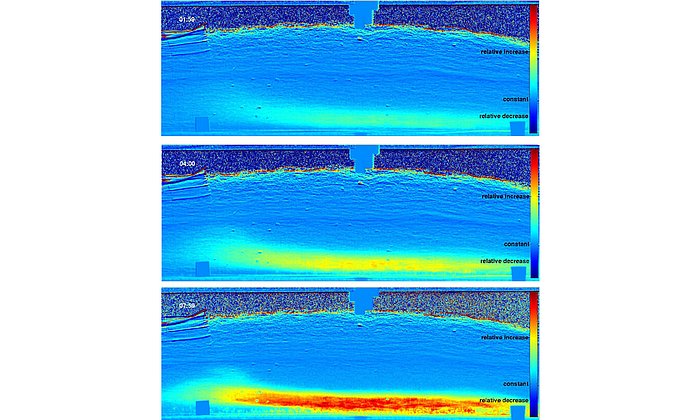

Seine Ergebnisse erstaunen: Nur bei den Proben eines depressiven Patienten, der mit Lithium behandelt worden war, beobachtete Josef Lichtinger eine höhere Anreicherung des Lithium in der sogenannten weißen Substanz. Das ist der Bereich im menschlichen Gehirn, in dem die Nervenbahnen laufen. Der Lithiumgehalt in der benachbarten grauen Substanz war 3-4-fach geringer. Die Lithium-Anreicherung in der weißen Substanz konnte bei mehreren unbehandelten depressiven Patienten dagegen nicht beobachtet werden. Das weist darauf hin, dass Lithium nicht wie andere Psychopharmaka im Zwischenraum der Nervenzellen wirkt, sondern in den Nervenbahnen selbst.

Nun will Josef Lichtinger weitere Gewebeproben an der Forschungs-Neutronenquelle in Garching untersuchen, um seine Ergebnisse zu bestätigen und zu erweitern. Am Ende des Projekts steht eine Landkarte des Gehirns eines gesunden und eines depressiven Patienten, die ortsaufgelöst die Lithiumanreicherung zeigt. So könnte man das Universalmedikament Lithium zukünftig noch zielgenauer und kontrollierter gegen psychische Erkrankungen einsetzen. Die Arbeit wird von der Deutschen Forschungsgemeinschaft (DFG) unterstützt.